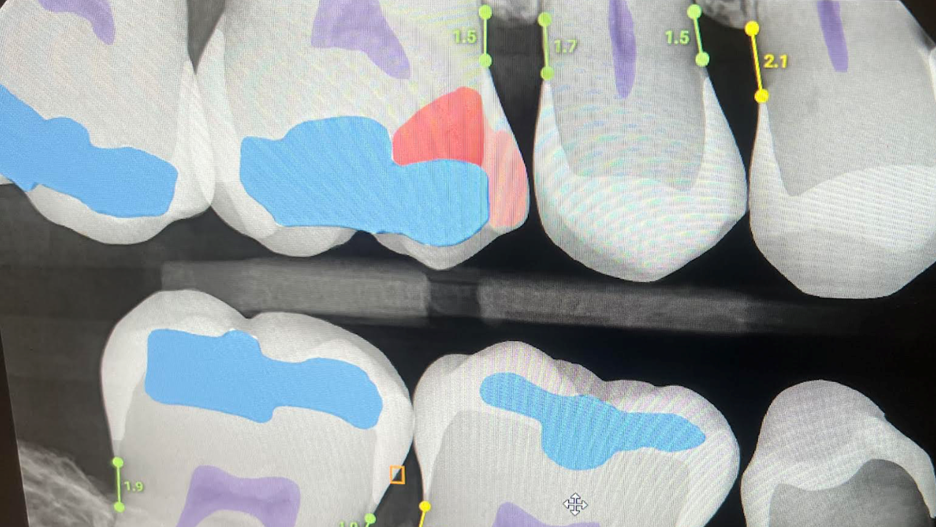

Overjet + Curodont for Incipient Decay

As you all know, I’m a big fan of Overjet.  A few months back, Rez challenged me with a question asking if we were power users of Overjet.  I didn’t think that as an organization we were.  As I dug more into it, I realized that we had just scratched the surface of utilizing Overjet. … Continued